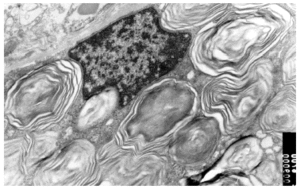

Se realizó una biopsia de una de las lesiones cutáneas cuyo estudio histológico mostró la presencia de vasos dilatados en el plexo vascular superficial de la dermis papilar. A mayor aumento se observaban abundantes vacuolas en el citoplasma de las células endoteliales (fig. 4). Todos estos hallazgos eran compatibles con angioqueratoma corporis diffusum. Se realizó un estudio analítico con hemograma y bioquímica, que incluyó las funciones renal y hepática, con valores dentro de los límites normales. Se evaluaron, además, los oligosacáridos en la orina que resultaron normales y se descartaron las glucoproteinosis (α y β -manosidosis, fucosidosis, aspartilglucosaminuria y sialidosis), gangliosidosis GM1 tipo 1, gangliosidosis GM2 tipo Sandhoff, galactosialidosis, enfermedad de Schindler y glucogenosis II, III y VI. El análisis enzimático en fibroblastos mostró unos valores normales para β -galactosidasa, hexosaminidasa y N-acetilneuraminidasa, con valores claramente disminuidos para α -galactosidasa (3,2 nmol/h/mg prot. frente a 56,5 del control), por lo que fue diagnosticado de enfermedad de Fabry. La madre del paciente presentaba unos valores en el rango de portadora (162 nmol/min/g de prot. frente a 1.144 del control). El análisis genético confirmó el estado de portadora y por lo tanto la heterozigosidad para esta enfermedad. Se practicó una biopsia renal cuyos hallazgos fueron compatibles a los referidos en la enfermedad de Fabry (fig. 5).

Fig. 5.--Imagen de microscopia electrónica de biopsia renal de la madre del paciente. Depósito de globotriaosilceramida renal.